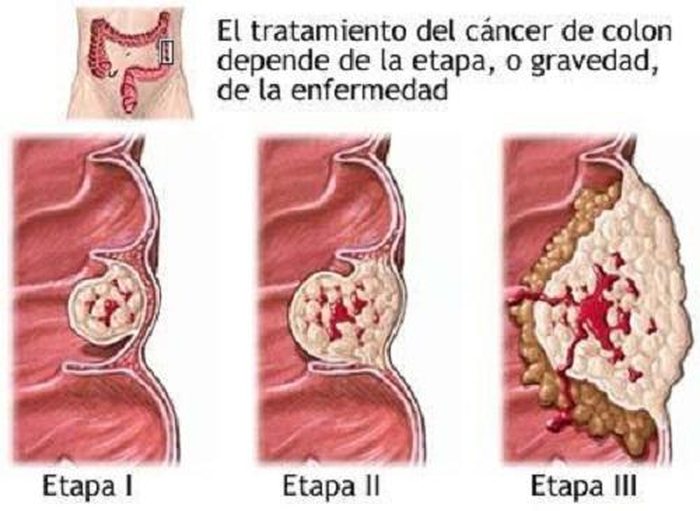

Desafortunadamente, el cáncer de colon es una enfermedad muy habitual generada por los malos hábitos de toda índole que la modernidad nos impone. El dilema nace porque ésta no es una enfermedad simple ya que puede provocar graves complicaciones e incluso la muerte. Pero lo que muchas personas no saben es que es posible prevenir la aparición del cáncer de colon de forma natural. Es por eso que el día de hoy hablaremos de ello y te enseñaremos todas las medidas para prevenir esta enfermedad.

Ahora, encontrarás una serie de consejos recomendados para evitar que esta enfermedad ataque a tu colon. El cáncer de colon puede prevenirse siguiendo ciertos hábitos, por fortuna, y además no son tan difíciles de seguir. Es más, las estadísticas recientes señalan que el cáncer de colon es el tercer tipo de cáncer más diagnosticado en Estados Unidos.

El motivo para que esto ocurra es que es muy común que este órgano acumule toxinas que lo terminan enfermando; no obstante, como la mayoría de los órganos de nuestro cuerpo, el colon tiene funciones vitales para nuestro organismo y por eso es importante cuidarlo.

No obstante, los malos hábitos de la modernidad están causando estragos ya que el cáncer en este órgano es la segunda causa de muerte en EEUU. La buena noticia es que esta enfermedad puede prevenirse simplemente modificando algunos hábitos cotidianos. Recomendaciones para prevenir el cáncer de colon